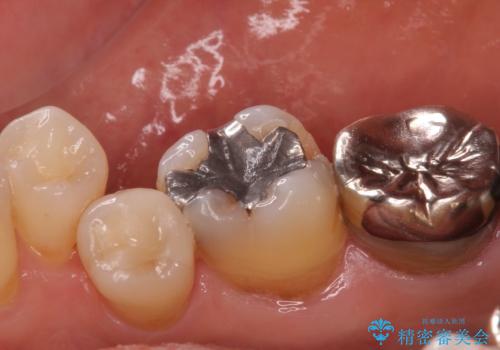

- 右下6 セラミックインレー:77,000円費用は治療当時の料金となります

白くて適合の良い詰め物が入ったことで大変喜んでいただけました。

奥の銀歯も今後やり変えていきたいとのご希望もいただきました。